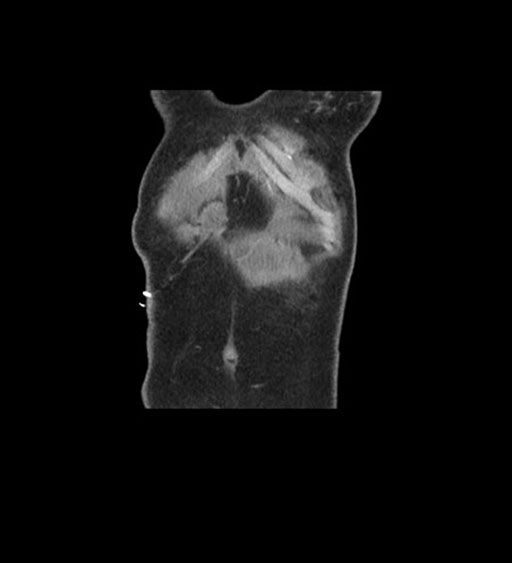

Coronal Arterial

Imaging analysis

Based on initial findings, which issue(s) would you be most concerned about?